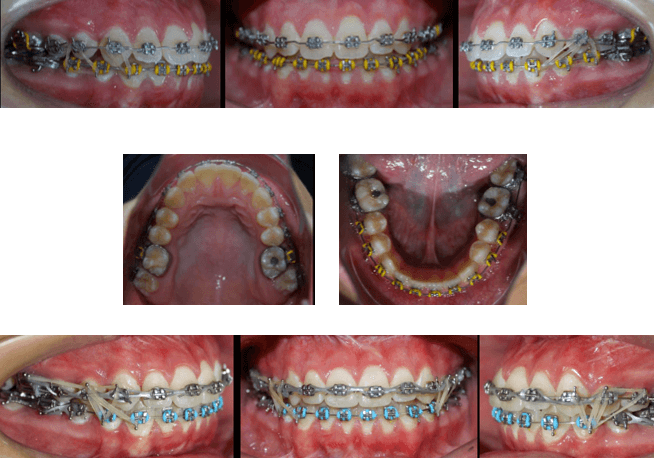

Fotografías Intraorales Pre Quirúrgicas

El paciente se ha tratado bajo el concepto de Surgery First ya que se realizó la intervención quirúrgica de forma temprana con una mínima alineación y nivelación, evitando las desventajas de una larga etapa de ortodoncia prequirúrgica.

Fase Ortodoncia Post Quirúrgica y Finalización

• Realineación y nivelación

• Consecucion de las Clase I molares y caninas

• Correcta ubicación de los dientes en sus bases oseas

• Torques y tips correctos

• Logro del correcto Overjet y overbite

En esta fase de Ortodoncia post quirúrgica donde se aprovecho el fenómeno de Aceleración Regional que se activa gracias a la cirugía ortognática y se lograron los objetivos oclusales, funcionales y estéticas en poco tiempo.